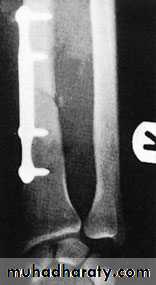

Unless the fragments are in close apposition, reduction is difficult and re-displacement in the cast almost invariable. So open reduction and internal fixation from the outset.

The fragments are held by interfragmentary

compression with plates and screws. Bone grafting is advisable if there is comminution.

It takes 8–12 weeks for the bones to unite.

Adult fracture treatment